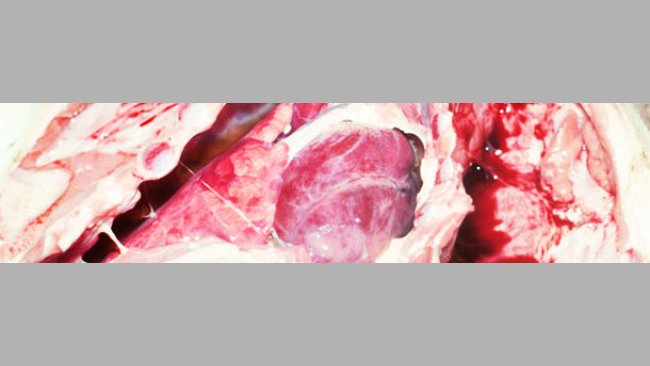

Nos avisan de varios cebaderos integrados en una empresa española en los que han aparecido de forma súbita un porcentaje elevado de cerdos muertos.